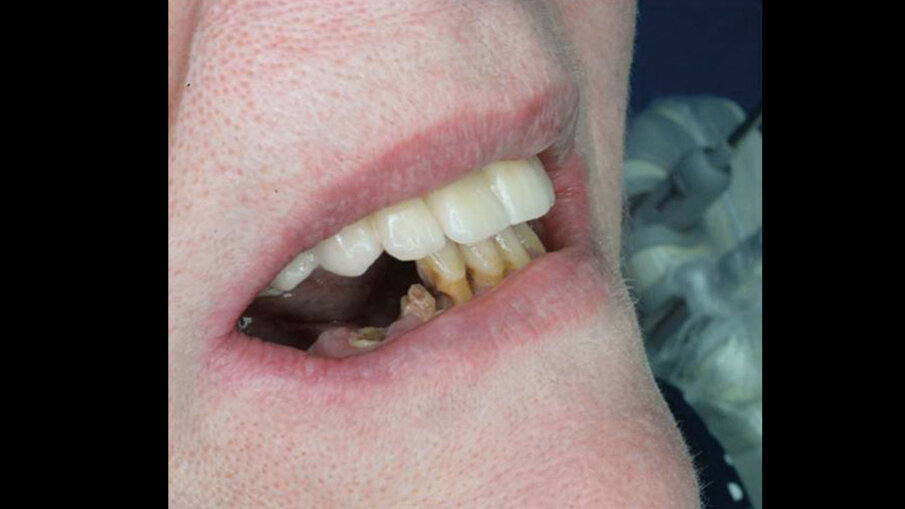

La paziente, una donna di 69 anni in buono stato di salute generale e senza terapie farmacologiche in corso, presentava una condizione orale fortemente compromessa caratterizzata da molte estrazioni dentali pregresse, una dentatura residua gravemente danneggiata da carie distruttive e numerosi processi infiammatori apicali e periapicali, che comportavano una severa mobilità della maggior parte dei denti presenti (Figg. 1, 2). La paziente utilizzava già una protesi parziale mobile superiore, la quale aveva causato nel corso degli anni un’ampia area di decubito palatale (Fig. 3). Data la compromissione estetica e funzionale dell’intero apparato masticatorio, si è deciso di procedere con una riabilitazione mediante una protesi avvitata supportata da impianti.